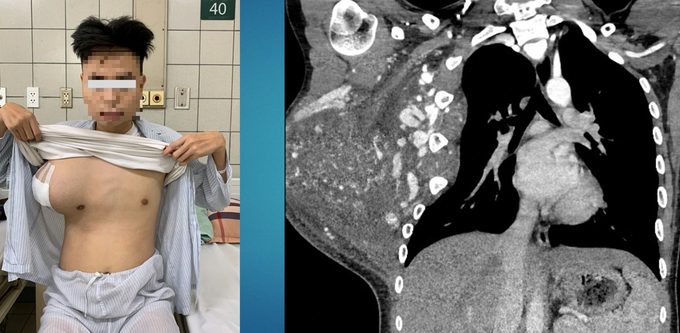

| Khối u khủng 'dính' trên ngực bệnh nhân nhiều năm nay khiến cuộc sống và học tập của cậu bé MInh Tú bị ảnh hưởng rất nhiều. Ảnh: sức khỏe và đời sống. |

Ths.BS Ngô Gia Khánh, Trưởng khoa Phẫu thuật lồng ngực - mạch máu thông tin trên báo Dân Trí , bệnh nhân được đưa đến Bệnh viện Bạch Mai hôm 24/2, trong tình trạng có khối u khổng lồ lồng ngực, tăng sinh nhiều mạch máu.

Trước đó, từ năm 2018, khi đang học lớp 6, bệnh nhi được phát hiện có khối u 3-4cm ở vùng ngực, đã đi khám tại Bệnh viện Ung bướu TPHCM, chẩn đoán u mạch máu, chỉ theo dõi tiến triển.

Sau 4 năm, khối u to lên, bệnh nhân được đưa đến nhiều Bệnh viện ở TPHCM nhưng không có phương pháp điều trị tối ưu. Ảnh hưởng 2 năm Covid-19, việc theo dõi bị gián đoạn. Đến đầu năm 2023, khối u ngực to lên nhanh, căng đau, gây ảnh hưởng sinh hoạt, học tập của bệnh nhân.

| Khối u kéo lệch lồng ngực, ăn rộng ra bả vai. - Ảnh: dantri. |

"Khi tiếp nhận bệnh nhân, chúng tôi cũng bất ngờ bởi một khối u khủng chiếm trọn một bên ngực, ăn rộng, xâm lấn ra xương bả vai, chèn ép vào thành ngực. Đặc biệt, khối u tăng sinh mạch máu rất nhiều, để xử lý sẽ có nguy cơ chảy máu ồ ạt", BS Khánh thông tin.

Trên thế giới, một số trường hợp có khối u tương tự đã được báo cáo dưới dạng các ca lâm sàng, tuy nhiên, không ca nào ghi nhận khối u kích thước lớn như trường hợp này.

Sau ca mổ đầy khó khăn, các bác sĩ đã lấy ra được khối u thành ngực nặng hơn 3kg. Kết quả giải phẫu bệnh sau đó cho thấy là bệnh u mạch trong cơ, đây là tổn thương lành tính rất hiếm gặp, chiếm 0,7% các ca bệnh lành tính ở thành ngực.